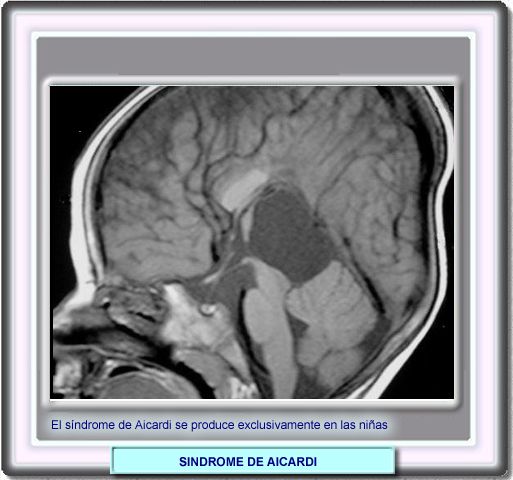

DE AICARDI

El síndrome de Aicardi es un desorden hereditario ligado al cromosoma X caracterizado por una tetrada de síntomas:

Es una enfermedad que se produce casi exclusivamente en las niñas debido a la elevada mortalidad embriónica de los varones. |